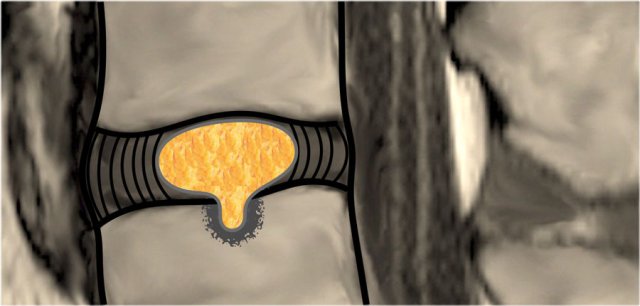

Intravertebral herniation

Intravertebral herniation or Schmorl node is herniation of disc material in the vertical direction through a gap in the vertebral end plate.